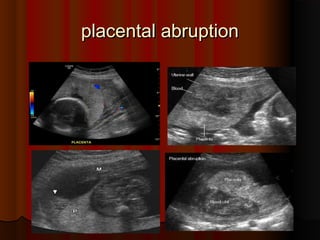

placental abruptionplacental abruption.. Crescent ofCrescent ofavascularavascular low echogenicitylow echogenicity between placenta andbetween placenta and uterine wall consistentuterine wall consistent withwith placentalplacental abruptionabruption..